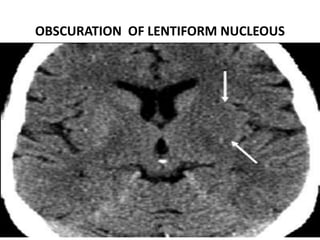

OBSCURATION OF LENTIFORM NUCLEUS

• Lentiform nucleus appears hypoattenuated because

of acute ischemia of the lenticulostriate territory ,

resulting in obscuration of the lentiform nucleus.

• This feature may be seen on CT images within 2

hours after the onset of a stroke .

OBSCURATION OF LENTIFORM NUCLEOUS